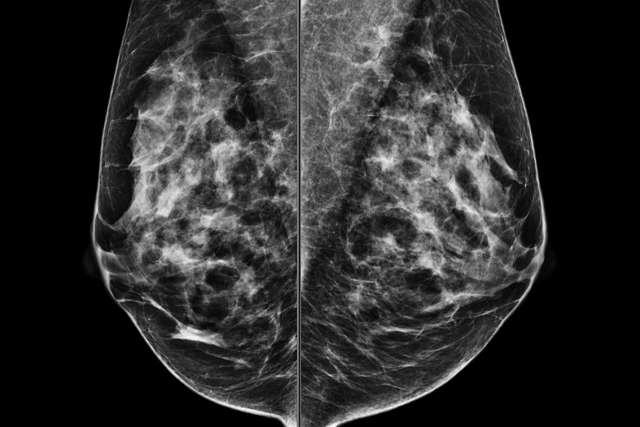

Welcome: Welcome to the UCLA Breast Radiology Educational Website, a comprehensive and reliable source of information for residents, fellows, and physicians seeking to expand their understanding of breast radiology.

Who We Are: Our team of radiology residents and fellows, mentored by fellowship-trained UCLA breast radiology faculty, have developed a rich collection of clinical cases and articles that summarize key concepts in breast radiology, citing recent and significant studies in the field.

Our Goals: Our website is committed to delivering digestible, evidence-based educational content that empowers healthcare professionals to provide the best possible care to their patients. We invite you to join us on this exciting journey of learning and excellence in breast radiology.